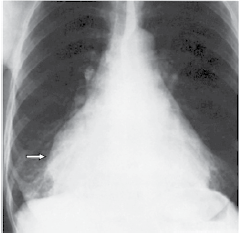

Mulher, 50 anos, é encaminhada ao cardiologista para avaliar paciente com cansaço aos esforços. Realizou a seguinte radiografia, no Pronto-Socorro, uma semana antes:

(Arquivo pessoal; imagem usada com autorização)

A seta indica qual estrutura?